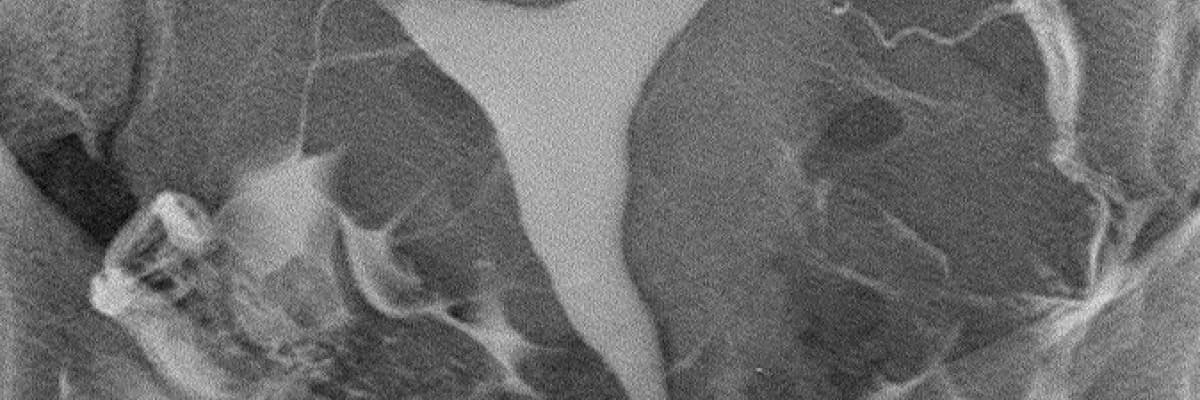

HSG (rahim filmi) incelemesi 50 seneden uzun süredir bilinmekte ve uygulanmaktadır. Buna karşılık son 20 yılda pek çok teknolojik ilerleme olmuş, buna uygun aparatlar üretilmiş ve yeni teknikler geliştirilmiştir. Söz konusu yenilikler şu başlıklar altında toplanabilir:

Bütün bu yenilikler, ağrısız rahim filmi çekimini mümkün kılmakla kalmamış, olumsuz yan etkiler çok azalmış, bazı komplikasyonlar ortadan kalkmış, gerek uygulamayı yapan hekimlerin gerekse hastaların maruz kaldığı radyasyon miktarları belirgin derecede düşmüş, film kalitesi yükselmiş, doğru teşhiş oranı yükselmiş, inceleme sayılarının artmasıyla birlikte birim maliyetler ve fiyatlar göreceli olarak düşmüştür. Yeni tekniklerin oldukça yüklü yatırım maliyetinin olmasına rağmen bir paradoks olarak eski teknik kullanılarak yapılan standart incelemelerin toplam birim maliyeti yeni tekniklerden daha ucuz olamamaktadır.

Sonuç olarak, rahim filmi çekimi için C kollu dijital röntgen cihazı bulunan ve yukarıda sayılan yeni teknikleri kullanan merkezler tercih edilmelidir.